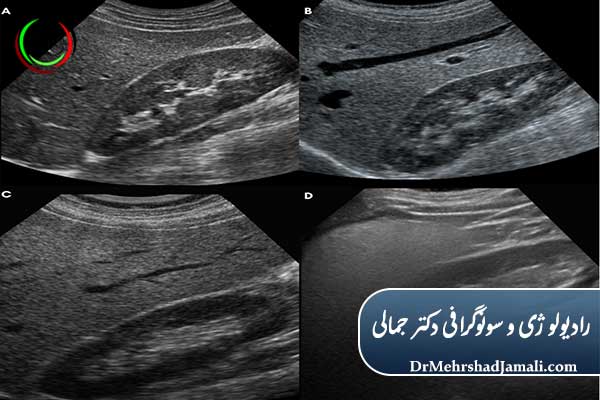

1. سونوگرافی کبد

سادهترین و رایجترین روش—میزان چربی و گرید بیماری دیده میشود.

مطلب مرتبط : تفسیر نتایج سونوگرافی کبد